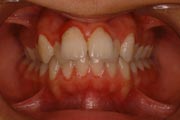

Crowding

Before